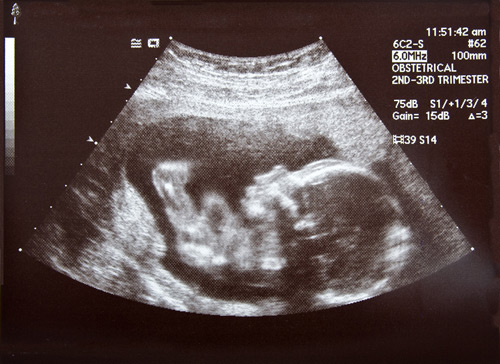

Ultrasound

A pregnancy ultrasound is a non-invasive test that scans the unborn baby and the mother's reproductive organs using high frequency sound waves.

• The sound waves are then translated into a two-dimensional picture on a monitor. The mother doesn't feel or hear the transmission of the sound waves.

• By measuring the baby's body parts, such as head circumference and the length of long bones, the operator can estimate its gestational age.

Ultrasound testing can determine the age of your baby, detect the presence of twins, help determine your due date, and measure your baby's growth and development. Sometimes an ultrasound can determine your baby's gender, but not always. Your baby's gender may or may not be clearly apparent.

Obstetric ultrasound provides pictures of an embryo or fetus within a woman's uterus.

Parents now commonly see ultrasound movies or images in the first trimester and clinically this is a non-invasive prenatal diagnostic tool for detection of abnormalities as well as a method of staging (ageing) and checking growth. Ultrasound can also be used in combination with other techniques to locate both embryo and placenta for other prenatal tests

The movement of the embryo or fetus and the heart beat can be seen as an ongoing ultrasound movie. Most ultrasound devices also have an audio component that processes the echoes produced by blood flowing through the fetal heart, blood vessels and umbilical cord. This sound can be made audible to human ears and has been described by patients as a whooshing noise.